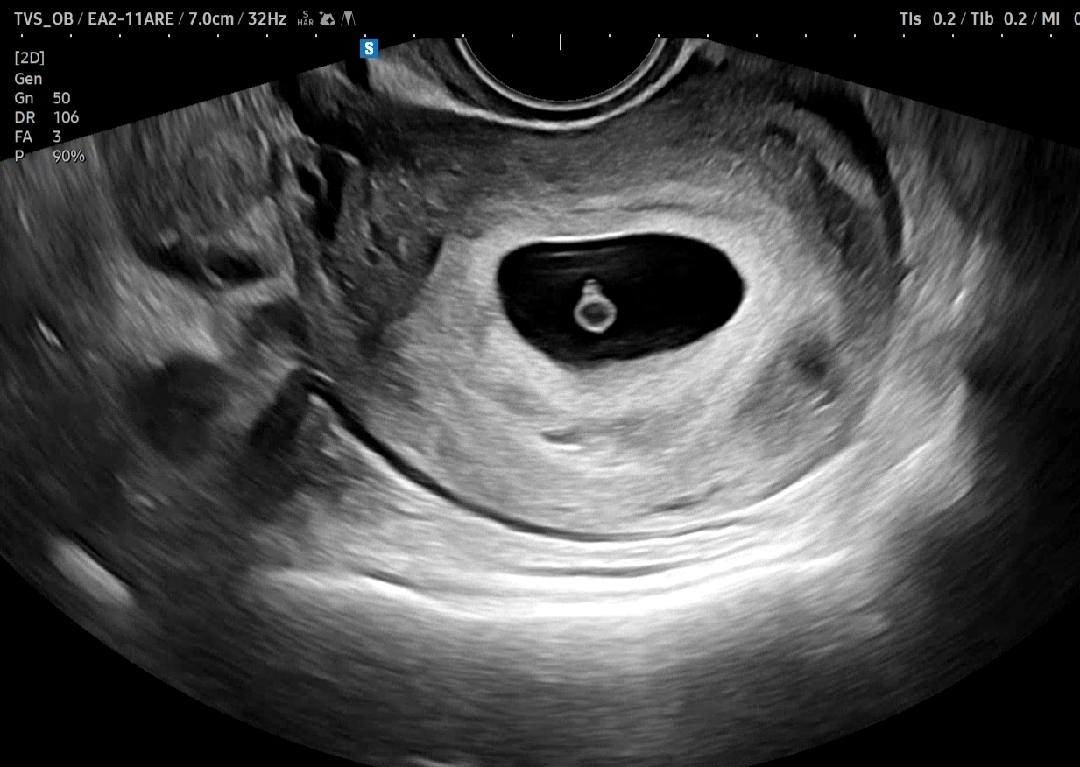

다이아반지+심장소리 확인했어요🩷

5주 5일차 다이아반지도 보고 심장소리도 듣고왔어요☺️ 제가 나이가 좀 있어 걱정했는데 피고임도 없고 아가는 3mm, 심장은 120 정도로 뛰고 있다고 봐주셨어요. 조그맣게 콩닥대는 심장이 너무나 신기했네요! 앞으로도 무럭무럭 잘 커주길🩷